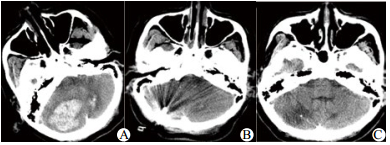

3.4 典型病例患者女,60岁零9个月,因“神志不清、呕吐、抽搐3 h”于2014年1月15日急诊入院。患者有高血压病史多年,服用硝苯地平缓释片控制血压,血压控制不详。有精神分裂症史。入急诊室时生命体征BP 220/140mmHg, P 62次/min, R14次/min, SaO2 90%, GCS评分5分,双侧瞳孔等大等圆,直径2 mm,光反射迟钝。立即给予气管插管,急诊头颅CT(图 1)示:①小脑出血(出血量约19 mL); ②梗阻性脑积水,拟“①高血压并小脑出血; ②高血压病3级,极高危; ③梗阻性脑积水”; 收住EICU病房。局麻下用YL-1型颅内血肿穿刺针行右侧脑室穿刺引流,缓解颅内高压。之后送CT室行小脑血肿定位,采用YL-1型颅内血肿穿刺+尿激酶液化术,手术顺利,清除血肿约10 mL, 术后予脱水降颅压、监控血压、抗感染、营养神经、亚低温、镇痛镇静对症支持治疗,4 d后患者神志转清,GCS12分,复查头颅CT, 小脑血肿基本清除,拔除颅内穿刺针。患者自主呼吸平稳,拔除气管插管,7 d后转普通病房治疗。随访3个月,GCS评分15分, 可缓慢步行,左侧肢体肌力5级,右侧肢体肌力4级, ADL-Barthel指数评定65分。

| A:术前,小脑出血约19 mL, 小脑实质、脑干受压,脑干周围池显示不清;B:术后1 d, YL-1型颅内血肿穿刺+尿激酶液化术后,小脑出血较前减少;C:术后1月,右侧小脑半球见片状低密度影,脑干环池结构恢复 图 1 女性患者头颅CT片 Figure 1 The CT picture of the female patients |